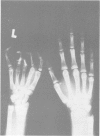

A 12 year old girl with the Poland syndrome and the 'morning glory' syndrome is described. The patient presented with absence of the left pectoralis major muscle, hypoplasia of the left arm, symbrachydactyly, and ipsilateral coloboma of the optic disc. This is the first report of the association of these two congenital anomalies.